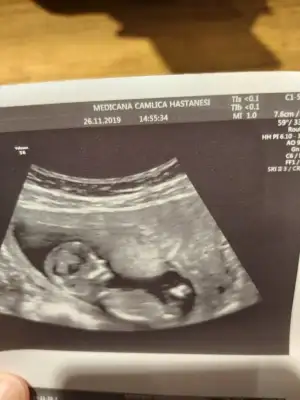

Erkek mi ki acabaTeyzeler bu da bizim fotomuz ☺